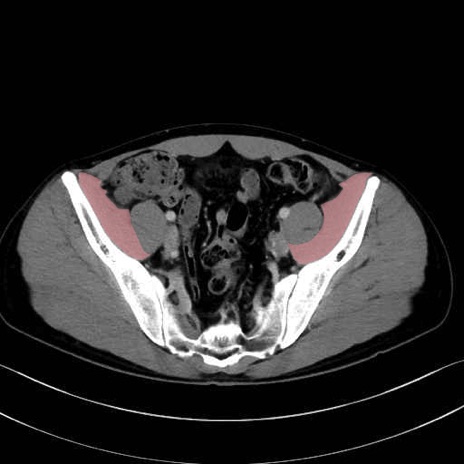

腸骨筋 (Iliacus)